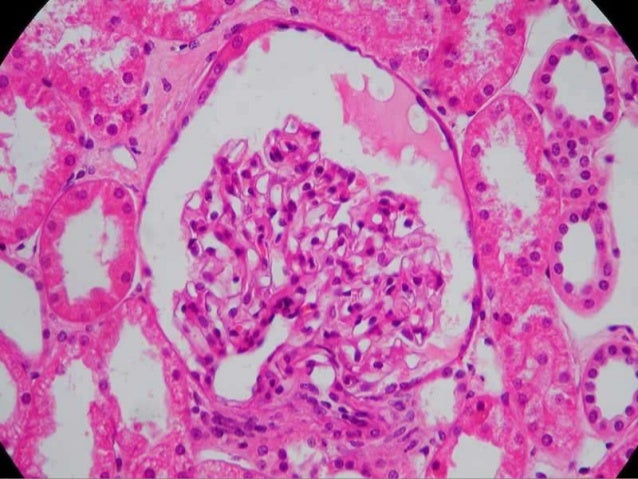

3. 3. CONSTITUIÇÃO Componentes do Sistema Urinário  Rins  Ureteres  Bexiga  Uretra 3

5. 5. RINS - FUNÇÕES 5 Filtração sanguínea;  Conservação dos metabólitos essenciais;  Secreção dos produtos residuais. Controlam o equilíbrio ácido-básico; Órgão endócrino – eritropoetina e renina.

13. 13. NÉFRONS - HISTOLOGIA Podócitos  Células do folheto visceral;  Tecido epitelial simples pavimentoso;  Aderidas à membrana basal dos capilares glomerulares. 13